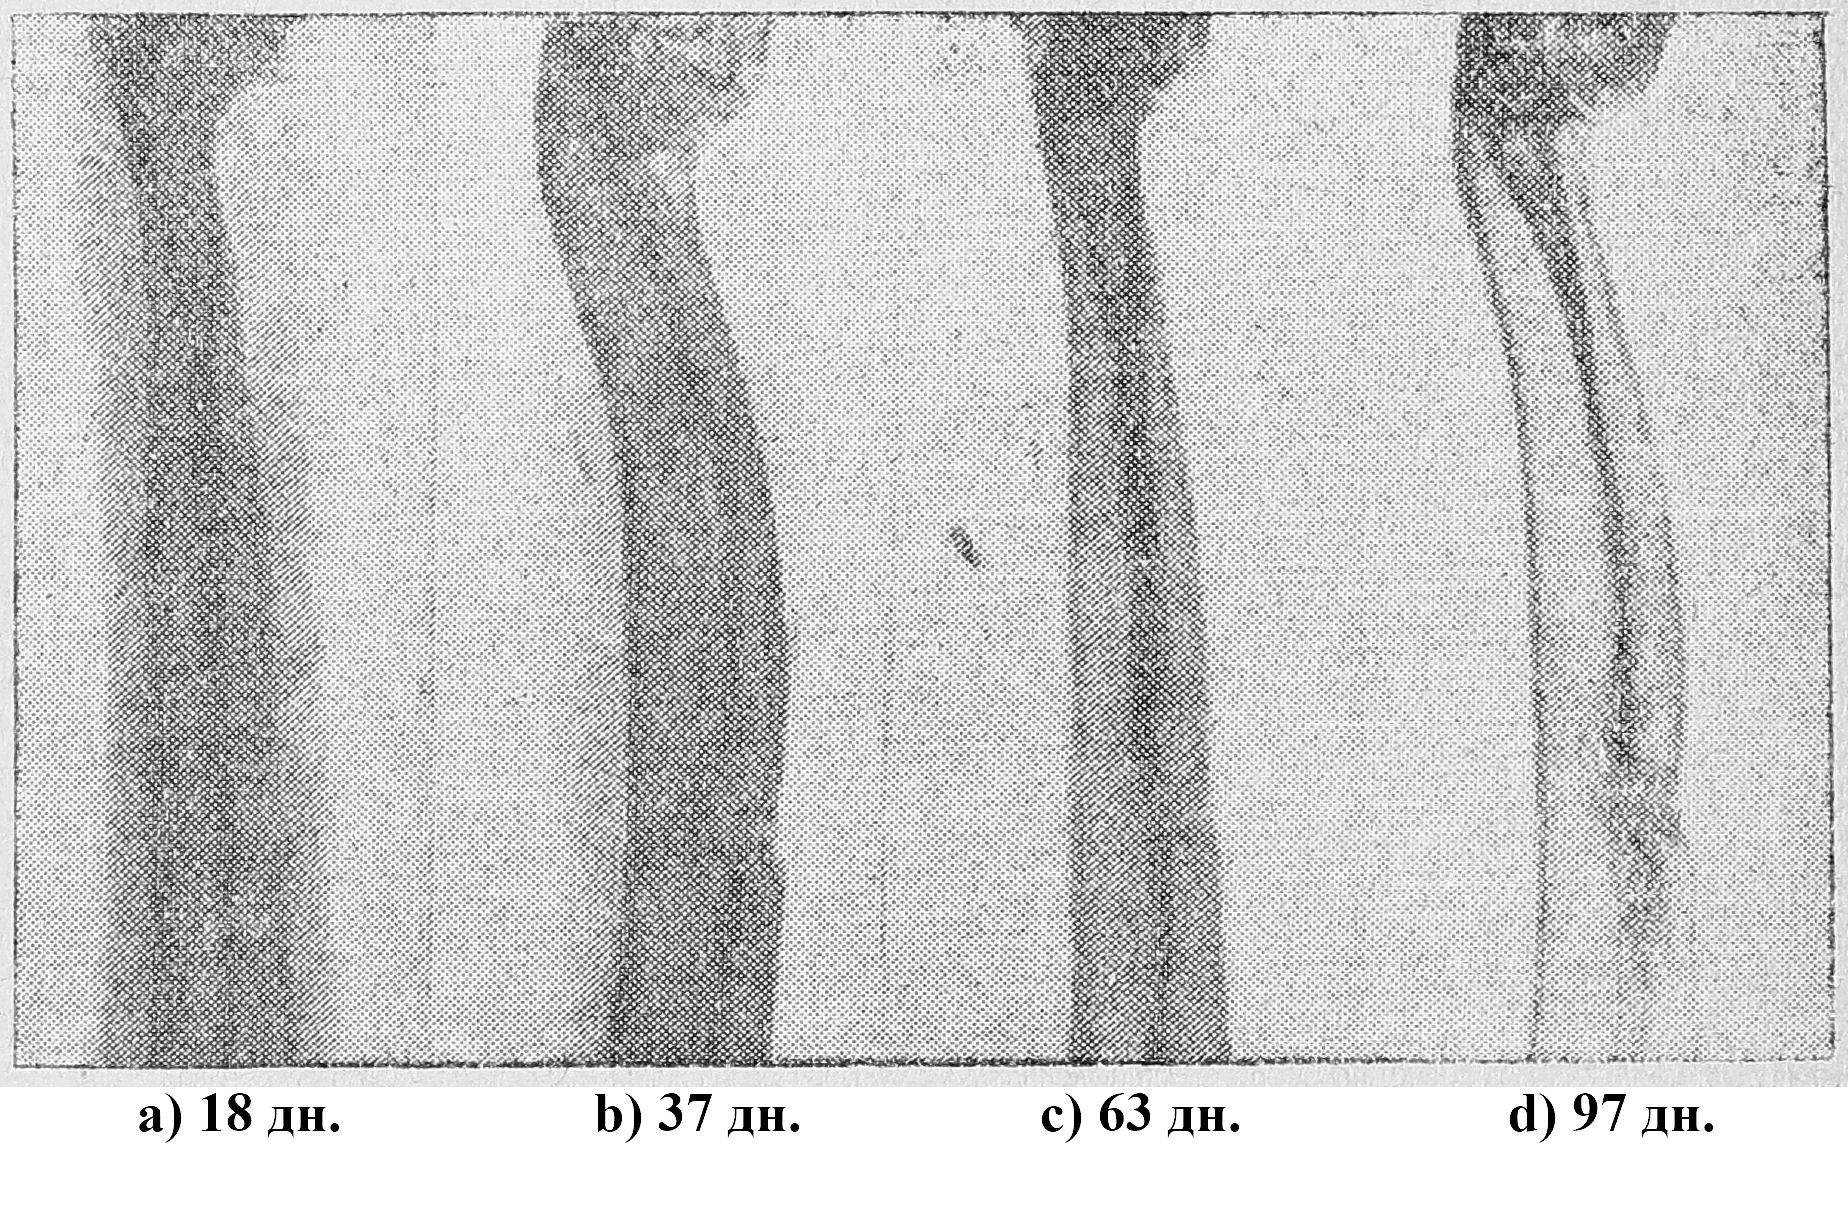

В соответствии с данными Бира, Шмидена, Жакова и др. наши опыты дали резко положительный эфект. При этом отмечалось значительное развитие периостальной мозоли и быстрое заполнение области дефекта (в среднем 43 дня) (см. р-грамму 4).

P-грамма № 4. Чистая кровь